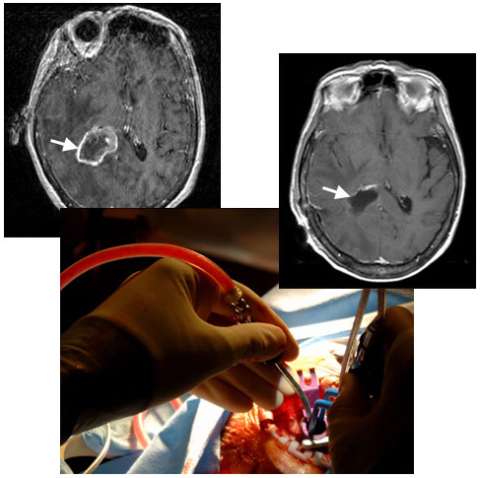

An MRI image (left) shows a metastatic brain tumor from lung cancer in the deep right parietal lobe (arrow). A photograph taken during surgery (center) shows the use of a minimally invasive port, only half an inch in diameter, to gain access so that the neurosurgeon can remove the tumor with minimal injury to the overlying normal brain. An MRI image following surgery (right) shows complete removal of the tumor (arrow) and the hardly visible surgical tract (below arrow).